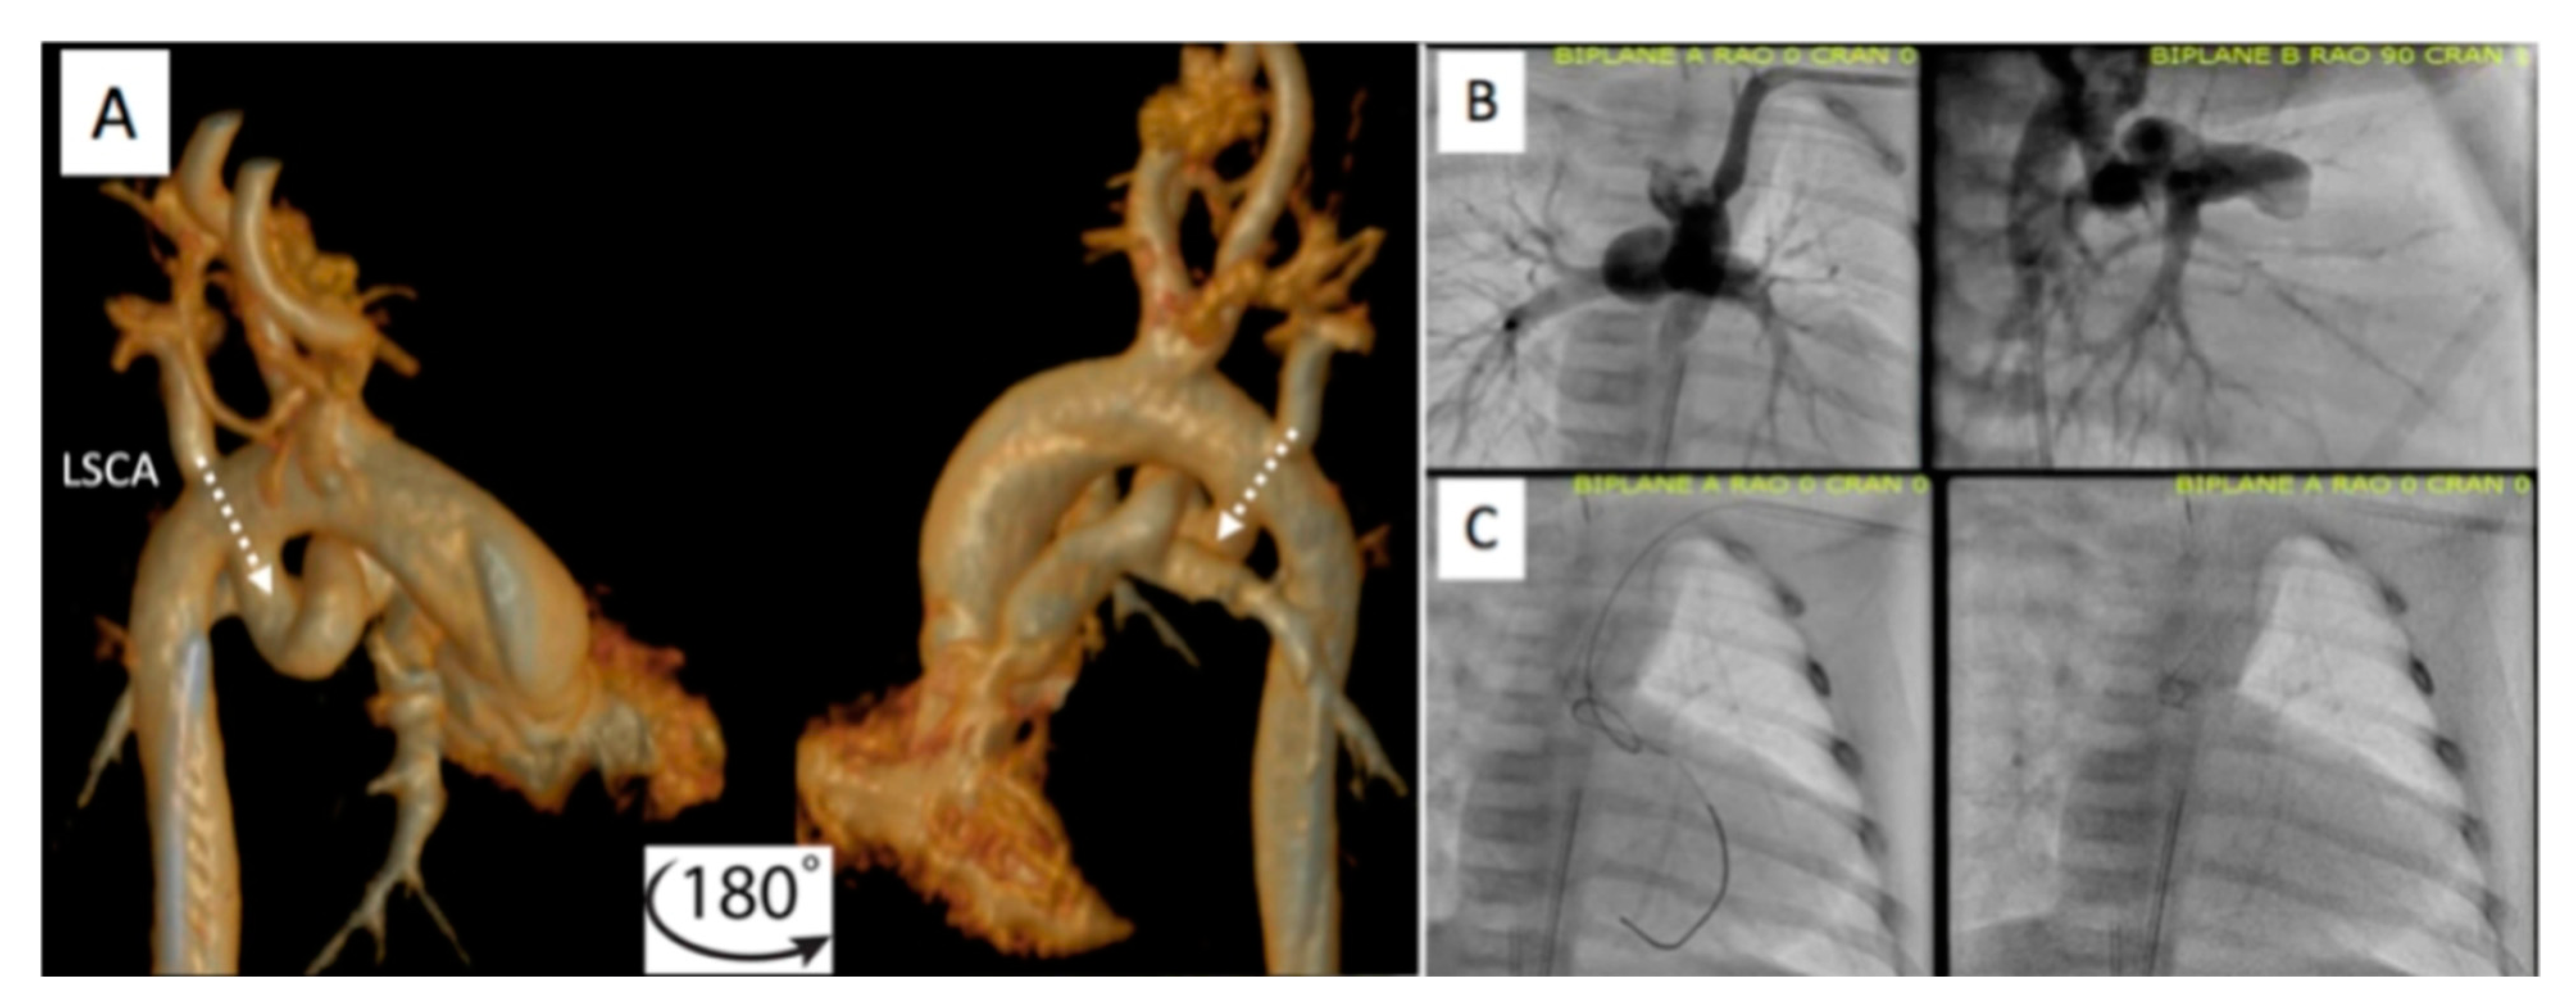

2.2. Patent Ductus Arteriosus (PDA) Stenting for Ductal-Dependent Pulmonary Blood Flow

2.2.1. Pre-Procedural

2.2.2. Post-Procedural

- Chamberlain, R.C.; Ezekian, J.E.; Sturgeon, G.M.; Barker, P.C.; Hill, K.D.; Fleming, G.A. Preprocedural three-dimensional planning aids in transcatheter ductal stent placement: A single-center experience. Catheter. Cardiovasc. Interv. 2019, 95, 1141–1148. [Google Scholar] [CrossRef]

- Qureshi, A.M.; Goldstein, B.H.; Glatz, A.C.; Agrawal, H.; Aggarwal, V.; Ligon, R.A.; McCracken, C.; McDonnell, A.; Bs, T.M.B.; Whiteside, W.; et al. Classification scheme for ductal morphology in cyanotic patients with ductal dependent pulmonary blood flow and association with outcomes of patent ductus arteriosus stenting. Catheter. Cardiovasc. Interv. 2018, 93, 933–943. [Google Scholar] [CrossRef]

- Arar, Y.; Dimas, V.V.; Nugent, A.W.; Hussain, T.; Kasraie, N.; Reddy, S.R.V.; Zellers, T.M.; Herbert, C. Pre-procedural CT imaging aids neonatal PDA stenting for ductal-dependent pulmonary blood flow with reduction in overall procedural morbidity. Cardiol. Young 2021, 1–6. [Google Scholar] [CrossRef]